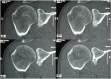

Axial computed tomography scan images following bony union of the free bone graft.